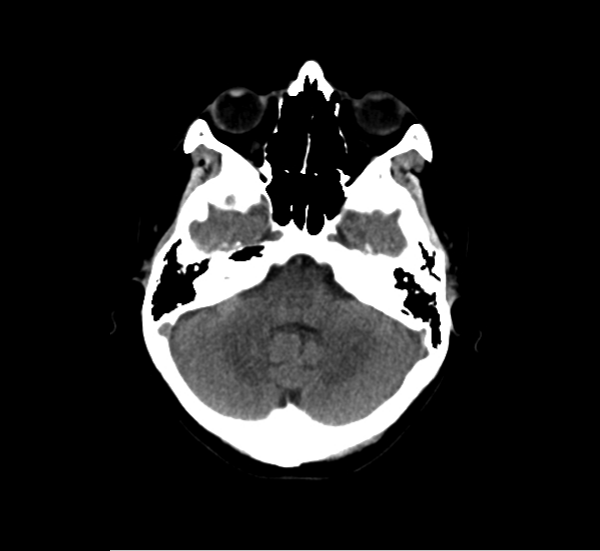

CT Brain Anatomy